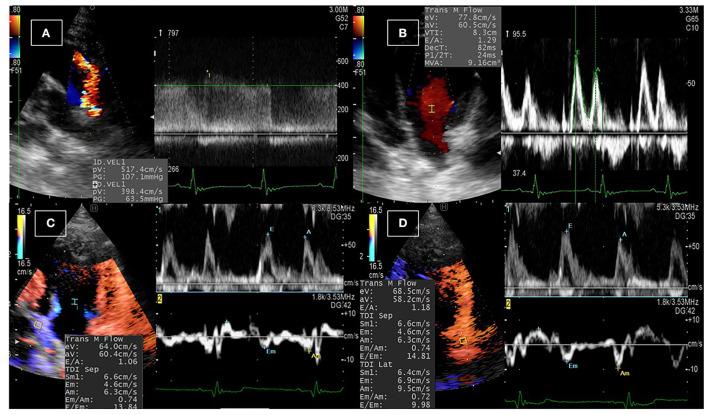

Novel non-invasive evaluation of the intraventricular pressure differences and gradients (IVPD and IVPG) by color M-mode echocardiography (CMME) is a promising method in diastolic function evaluation. Patent ductus arteriosus (PDA) is a congenital heart defect which is associated with increased preload. The present work provides a clinical trial for the assessment of IVPD and IVPG changes in dogs before and after surgical occlusion of PDA.

A total of 12 client-owned dogs were enrolled in this study. PDA was confirmed using echocardiography, and all dogs underwent PDA occlusion. Conventional echocardiography and CMME were conducted on each patient on the operation day (Pre-PDA) and 48 h after its occlusion (Post-PDA). The total IVPD and total IVPG, as well as segmental intraventricular pressure (basal, mid-to-apical, mid, and apical) were measured from Euler's equation using specific software (MATLAB). Data were analyzed for variability and for the difference between pre- and post-PDA. The effect of PDA occlusion on the measured variables was calculated using biserial ranked correlation (rc).

There was a significant reduction in end-diastolic volume, fraction shortening, stroke volume, and mitral inflow velocities (early and late) after PDA closure. CMME was feasible in all dogs, and the CMME indices showed moderate variability, except for the apical segment of IVPD and IVPG. After PDA closure, in comparison with the pre-PDA occlusion, there was a significant reduction in total IVPD (2.285 ± 0.374 vs. 1.748 ± 0.436 mmHg; = 0.014), basal IVPD (1.177 ± 0.538 vs. 0.696 ± 0.144 mmHg; = 0.012), total IVPG (1.141 ± 0.246 vs. 0.933 ± 0.208 mmHg; = 0.032), and basal IVPG (0.578 ± 0.199 vs. 0.377 ± 0.113 mmHg; = 0.001); meanwhile, mid, mid-to-apical, and apical segments of both IVPD and IVPG showed non-significant difference. The magnitude of PDA occlusion on the measured variables was clinically relevant and associated with a large effect size on total and basal IVPD and IVPG (rc > 0.6).

The current clinical study revealed matched response of IVPD and IVPG to the reduced preload rather than left ventricular relaxation. This result is an initial step in the clinical utility of CMME-derived IVPD and IVPG measurements in the diastolic function evaluation in dogs with PDA that warrants further clinical studies.